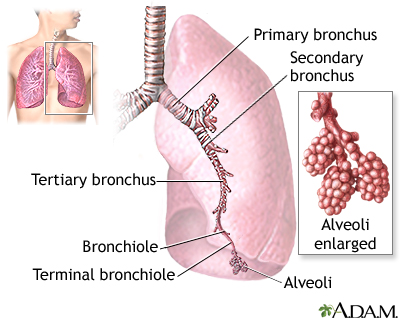

Pulmonary aspergilloma is a mass caused by an infection by the fungus aspergillus. It usually grows in preexisting lung cavities. The infection can also appear in the brain, kidney, or other organs.

Aspergillosis is an infection caused by the fungus aspergillus. Aspergillomas are formed when the fungus grows in a clump in a lung cavity. The cavity is often created by a previous condition. Cavities in the lung may be caused by diseases such as: